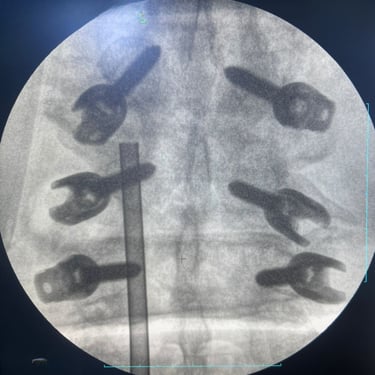

🧠 Listesis L4–L5 con Estenosis Severa: Estabilización con Fijación Transpedicular (FTP) y Fusión Intersomática Transforaminal (TLIF)

La listesis L4–L5 con estenosis severa provoca dolor lumbar e inestabilidad con compresión nerviosa. La fijación transpedicular (FTP) y la fusión intersomática transforaminal (TLIF) permiten descomprimir el canal espinal, estabilizar la columna y mejorar la función de forma segura y progresiva.